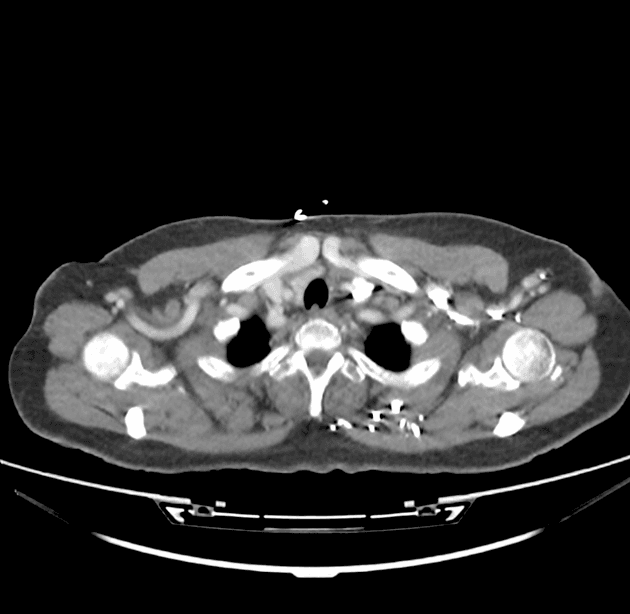

Hai lòng mạch riêng biệt với sự khác biệt về cường độ tín hiệu, tạo nên hình ảnh "động mạch chủ hai lòng" (double barrel aorta) được quan sát thấy trên các dãy ảnh MRCP.

Chụp cắt lớp vi tính động mạch chủ (CTA) xác nhận tình trạng bóc tách động mạch chủ type B (Stanford B). Vị trí bóc tách bắt đầu ở đoạn động mạch chủ phía dưới (distal) gốc động mạch thân cánh tay đầu (brachiocephalic trunk), kéo dài đến động mạch chậu chung trái.

Lòng giả (false lumen) lan vào động mạch thận trái, gây giảm tưới máu (reduced perfusion), phù hợp với hiện tượng giảm tăng quang của thận trái so với bên đối diện.

Ghi nhận hẹp đáng kể (significant stenosis) ở gốc động mạch thân tạng (coeliac trunk).

Động mạch mạc treo tràng trên (SMA) được làm đầy bởi lòng thật (true lumen), không thấy hẹp đáng kể.